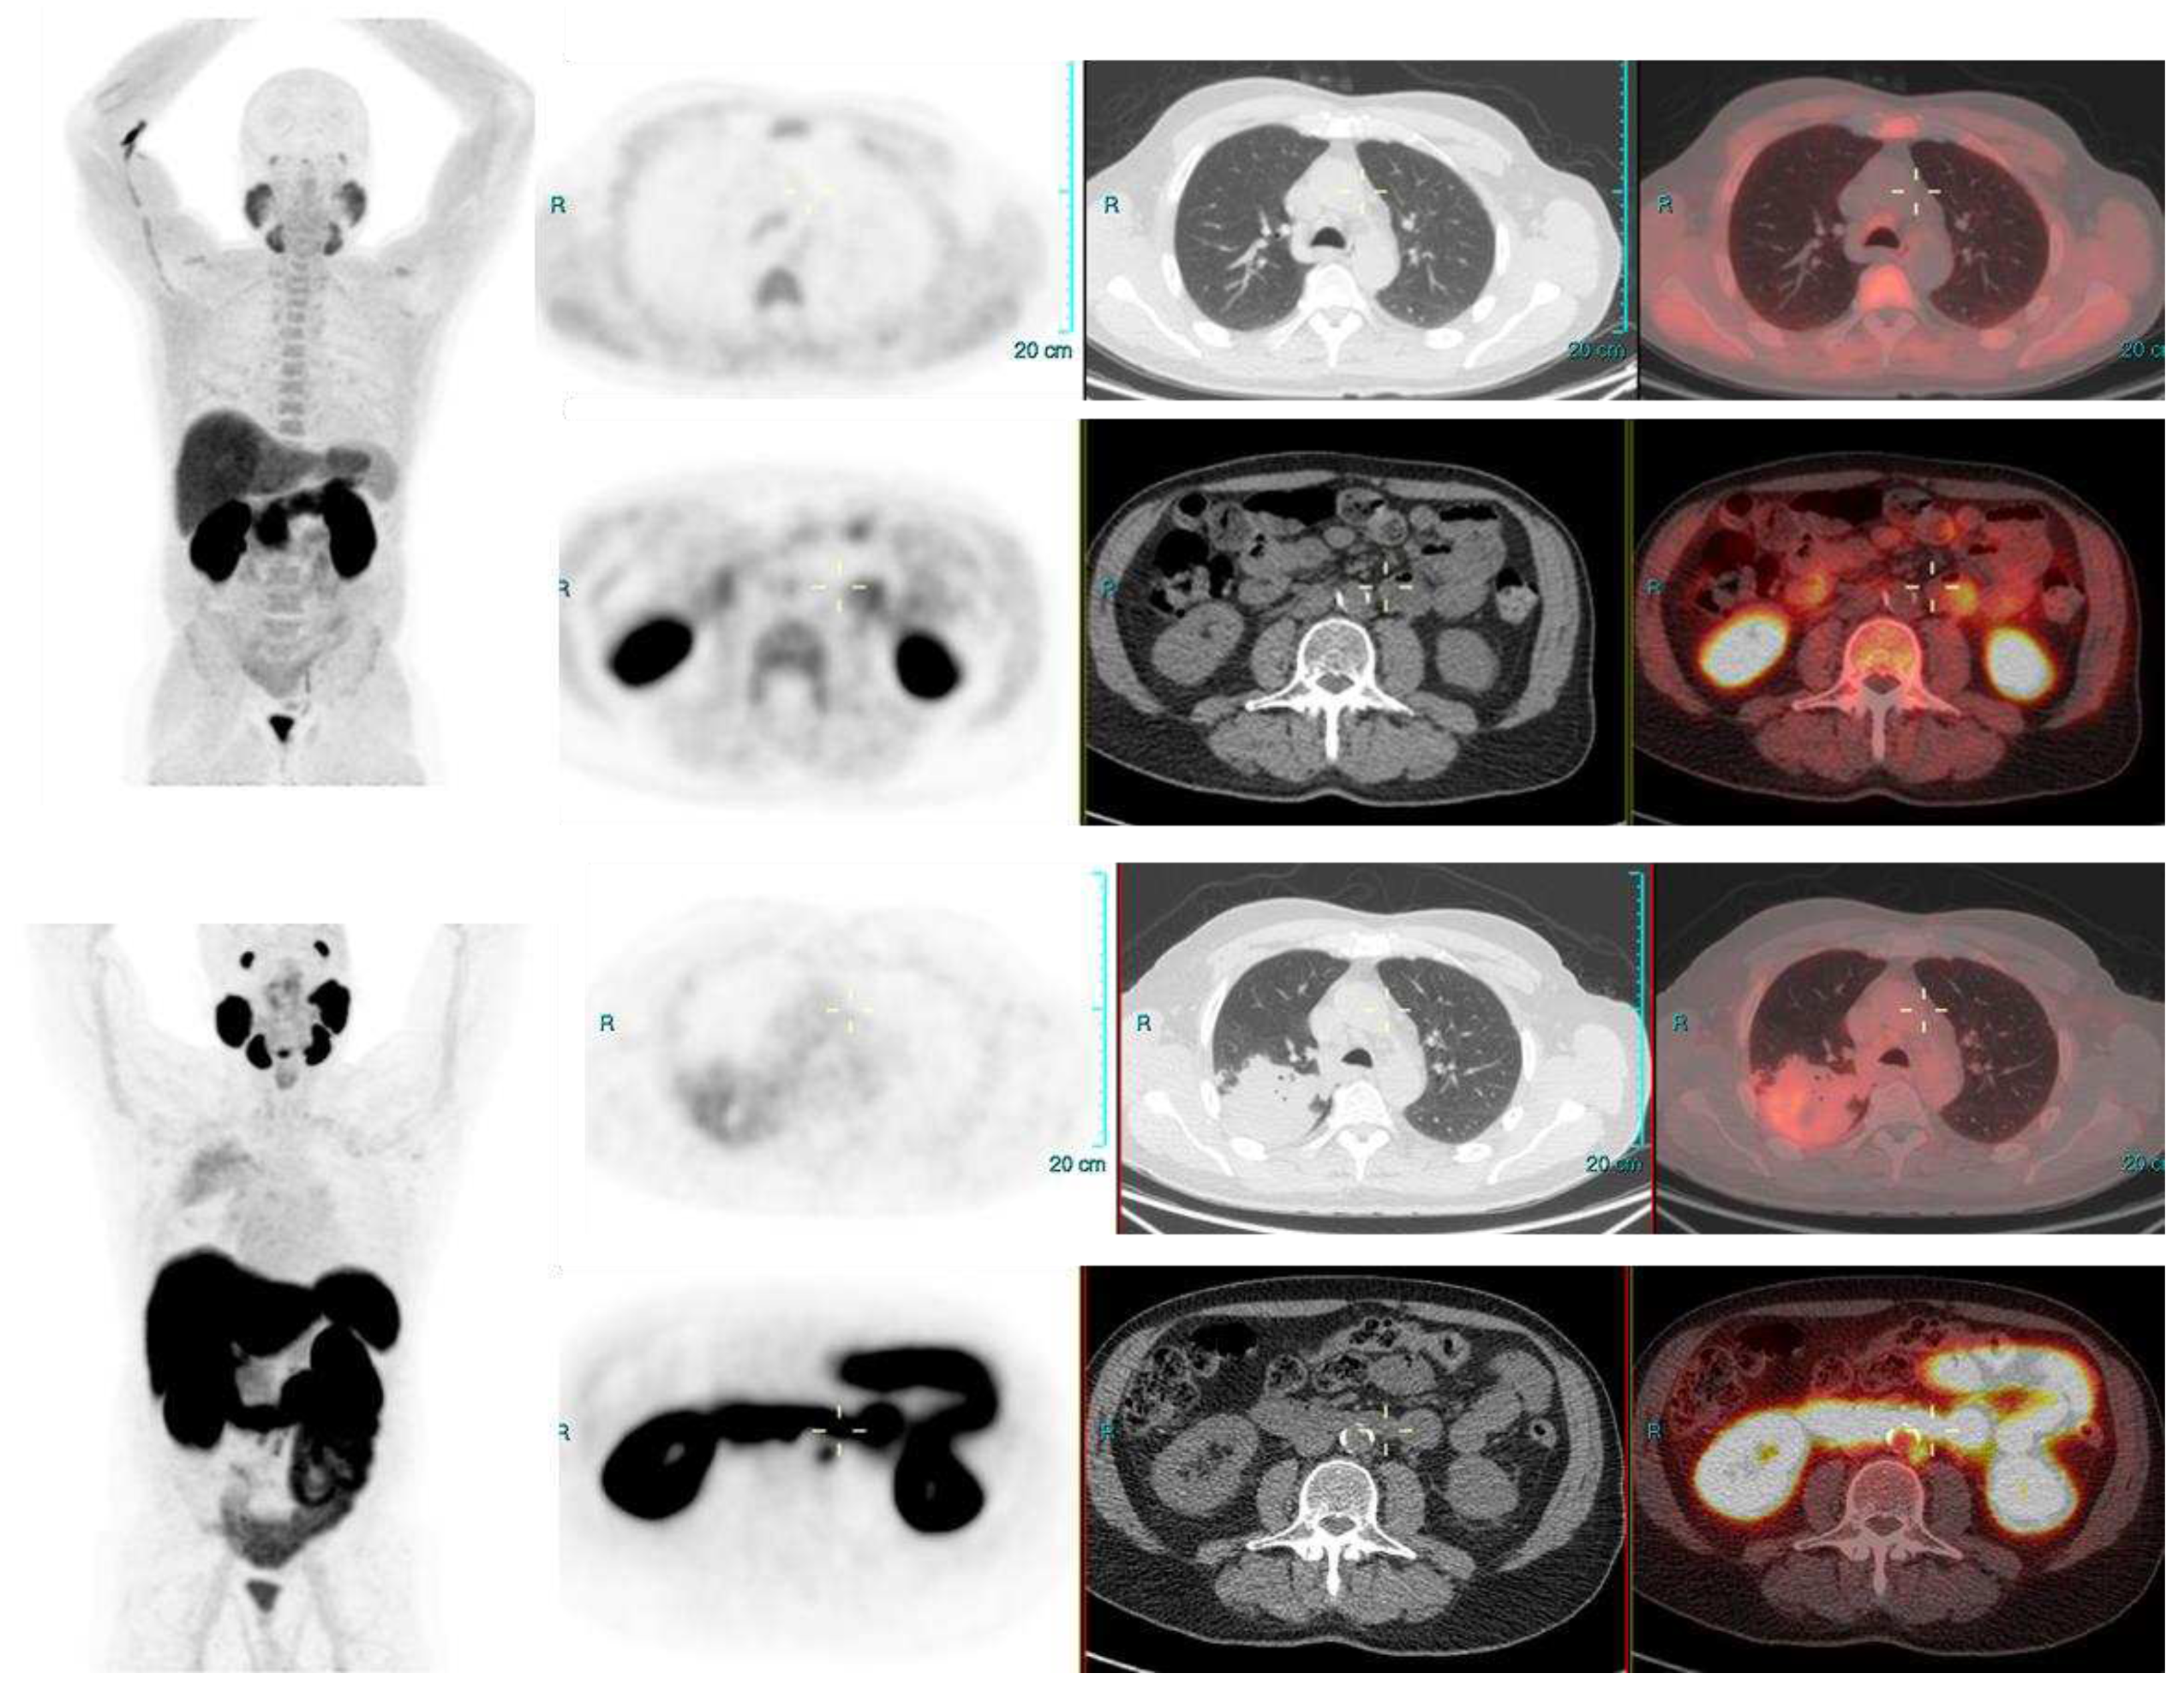

In 179 positive scans, highest number of positive findings were seen in lymph nodes with pelvic lymph nodes (112/179 scans) being most involved; 35 only had pelvic lymph nodes, 6 had only pelvic and retroperitoneal lymph nodes, and in rest pelvic lymph node were involved in various combinations along with involvement of prostate bed, bones and soft tissue. Among this positive PET CT group (Table 3); 67 had radical prostatectomy and in these PSMA avid lesions were seen most in pelvic lymph nodes with only pelvic lymph node in 33, prostate bed and pelvic lymph nodes in 4, pelvic, retroperitoneal lymph nodes along with bones in 13 each, only bone involvement in 1 and only soft tissue involvement (lungs) in followed by pelvic, retroperitoneal lymph nodes along with bones (5 scans), prostate bed along with pelvic nodes (4 scans), only bones (2 scans) and bone with soft tissue involvement (1 scan). In 112 positive PET CT scans, in non-radical prostatectomy group, 25 had recurrence only in prostate, 17 had recurrence involving prostate and seminal vesicles (i.e. prostate bed) only; 28 had no recurrence in prostate gland and only pelvic lymph nodal (2 scan), pelvic and retroperitoneal lymph nodal (6 scans) or systemic recurrence were present (20 scans, bone, visceral metastases); while 42 patients had recurrence in prostate as well as extra prostatic sites. Overall, in this non-prostatectomy recurrence group, in 75 % population (84/112 scans) prostate gland was found to harbor a PSMA avid lesion while in 25% population recurrence did not involve prostate gland.

PSMA-PET CT is being increasing used in clinical practice and is slowly becoming indispensable in care of many PCa patients by overcoming the challenges of low sensitivity and specificity of conventional imaging modalities. Studies focusing on diagnostic performances of PSMA PET CT in BCR have reported high detection rates (75-81%) in detecting PSMA positive lesions. Xing Zhoe et al, while evaluating BCR in patient following RP have found high detection rate for patients after radical prostatectomy. In their study 79% patients showed at least one pathological finding on 18F-PSMA-1007 PET/CT [8]. Treglia G et al, performed a systematic review and meta-analysis for detection rate of 18F-labeled PSMA PET/CT in BCR of PCa and found a pooled diagnostic rate of 81% for 18F-labeled PSMA PET/CT [9]. Similarly, in our study we were able to detect PSMA avid lesions in 229/295 scans (77%) which included both positive and indeterminate lesions as per PSMA RADS criteria.

In our study, most commonly positive findings were seen in lymph nodes with pelvic lymph nodes being most commonly involved with rest of structural involvement being less in other combinations. Similar observations have been seen in the previous studies [14,15,16]. Giesel FL et al while evaluating lymph nodal recurrence of prostate cancer found mean volume of lymph node was 0.5 ml. In 33% of their study population at least one node was larger than conventional criteria for morphological positivity. In their study 36 % patients had lymph nodes ≥8 mm and in patients with PSMA positive lymph nodes (67%) none of the PSMA-positive lymph nodes met the morphological criteria for positivity. In their study due to subcm, PSMA avid lymph nodes, the N stage was changed from N0 to N1 in 67 % of cohort on 68Ga-PSMA ligand PET CT [14]. Rahbar K et al [15], in their study while evaluating diagnostic performance of 18F-PSMA-1007 in patients with biochemical recurrent prostate cancer found, the patient-based sensitivity to be 95%. In their analysis also maximum number of recurrences were found in lymph nodes. They found a total, 213 lesions characteristic of PCa of which 37 were local relapses, 107 lymph node metastases, 67 bone metastases and 2 soft tissue metastases. In 29 patients’ relapse was seen exclusively in lymph node metastases. Sprute K et al, in their study of staging of prostate carcinoma in primary and biochemical recurrence found that in 34.4% of the cohort, positive lymph nodes were present on imaging. In their study the patient-based analysis showed a sensitivity of 85.9% and a specificity of 99.5% for lymph nodes larger than 3 mm [16]. We did not evaluate further the pattern of distant spread, correlation with pathology, PSA dynamics, levels in our current study as these have been studied in earlier studies with few showing their significances and few not, and further as this was not the aim of our study.